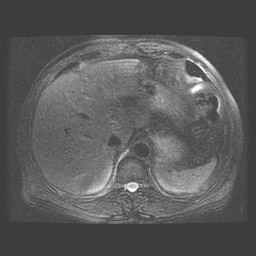

Abdomen